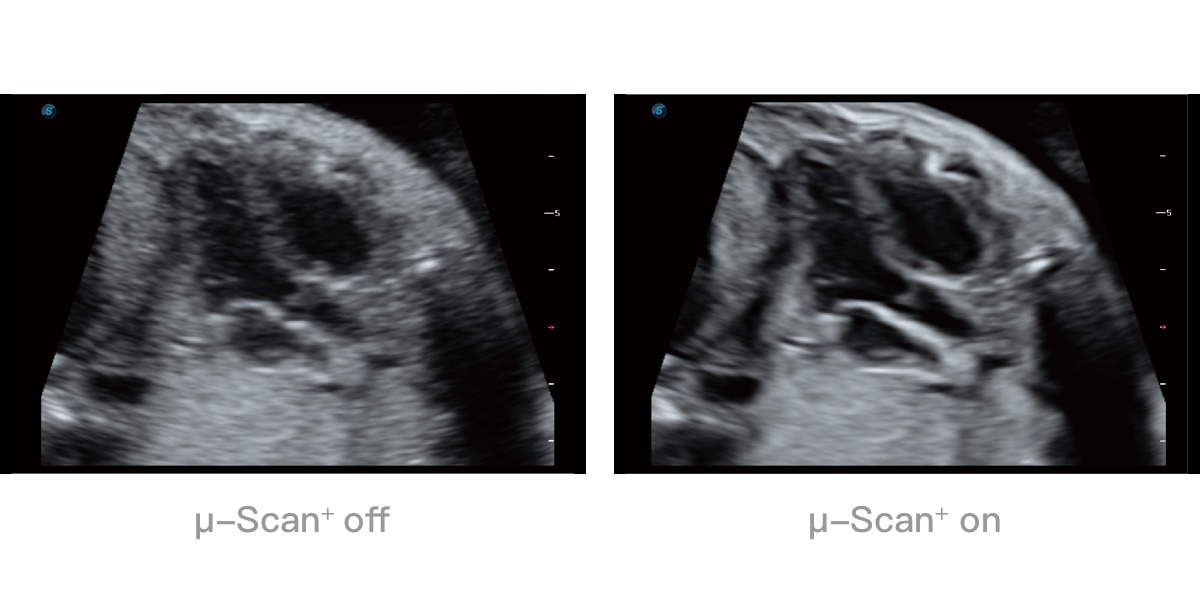

微米成像技术提升了对组织斑点噪声信号的抑制能力,并进一步强化边界信息,从而获得清晰图像。